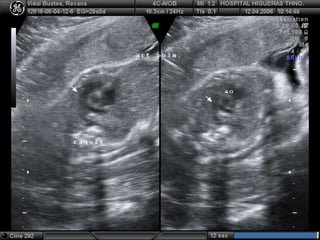

• 17.

 Debe versesiempre que DSM alcance los 16 a 18 mm  Medición de la CRL es el mejor parámetro para estimar edad gestacional  Edad gestacional:  42 + LEM en mm = Dias  6,5 + LEM en cm = Semana Rango de error +/- 5 dias